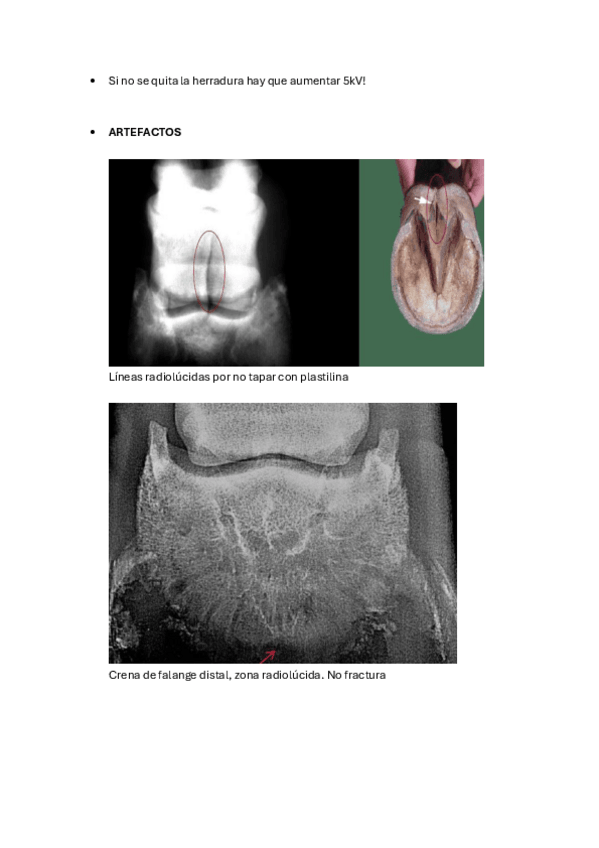

MT EQUINO

He publicado nuevos apuntes de 3º Diagnóstico Por la Imagen: MT EQUINO

Patologias.pdf

Apuntes-extra.pdf

Proyecciones.pdf